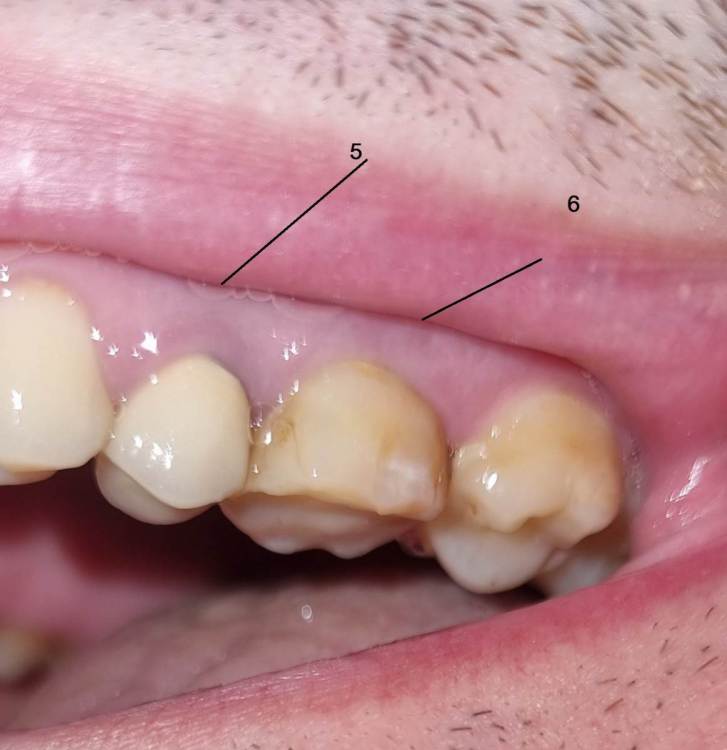

Chelovek2012 Опубликовано 17 апреля, 2023 Поделиться Опубликовано 17 апреля, 2023 (изменено) Всем добрый день. У меня вопрос. Верхняя левая 6-ка: Зуб давно был с запломбироваными каналами. Месяц назад их перепломбировали. Вкрутили в середину зуба какие-то как шурубчики для укрепления. И доктор говорит, что будет коронка Можно ли поборотся и спасти зуб, в который уже вкручены шурупчики для укрепления? 3 стенки зубы точно вижу на фото. Или нету смысла и он разлетится? Пломбировать уже нету смысла? Или технология пломбирования уже тут не подходит? 5 зуб возле него. Врачь говорит сразу сменить и эту коронку (ей 10 лет), так как между зубами есть нестыковка - темное место на рентгене между зубами Изменено 17 апреля, 2023 пользователем Chelovek2012 Ссылка на комментарий

Chelovek2012 Опубликовано 18 апреля, 2023 Автор Поделиться Опубликовано 18 апреля, 2023 (изменено) Спасибо. 3 Я просто думал, что в 2023 году уже есть технология сохранения зуба со стенками, чтобы не спиливать его и не ставить коронку. Зуб у меня новый не выростет больше никогда. Хотел поборотся за зуб. Скажите, а по фото/ренгтену можно ли определить, что коронка 5 зуба нуждается в замене? Изменено 18 апреля, 2023 пользователем Chelovek2012 Ссылка на комментарий

IvanK Опубликовано 20 апреля, 2023 Поделиться Опубликовано 20 апреля, 2023 20 часов назад, Chelovek2012 сказал: А это касается и других зубов, у которых есть только стенки? Нету технологии спасти зуб (во своих стенках) без коронки? покажите панорамный снимок (ОПТГ), тогда смогу сказать о других зубах судя по рг снимку есть все шансы получит кариес корня 5го зуба, что приведет к удалению зуба по поводу технологии спасения зубов - это только профилактика стоматологических заболеваний, а именно самостоятельная и профессиональная гигиена полости рта, своевременные осмотры и диагностические мероприятия у врача-стоматолога 1 Ссылка на комментарий